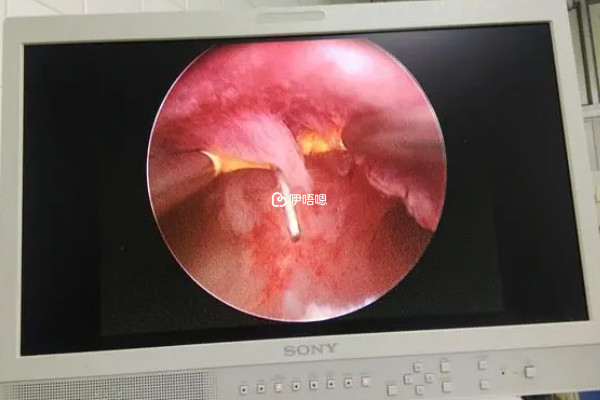

就目前來說,宮腔鏡檢查是比較常用的婦科檢查之一。該項檢查會利用鏡體的前部來進入女性的子宮內腔,然後把需要觀察的部位放大,讓婦科疾病或者病變的情況能夠更加直觀和準確的表現出來,所以其診斷準確性是比較高的。當然很多姐妹也比較納悶,在試管移植前為什麼要做公頃金檢查。一般來說其原因大致就如下:

宮腔鏡宮腔形態是一個圓形的腔隙,兩側宮角部看到兩個圓形的小孔,即輸卵管的開口,這樣的宮腔的正常的形態,它能夠正常孕育胎兒,反之若是其形態不正常的話,就會影響胎兒的正常生長與發育。

所謂的觀察子宮內膜環境,其實就是觀察子宮內是否有不利於胚胎髮育成長的因素,如是否有子宮內膜息肉、宮腔粘連或者是子宮縱膈等等,若是沒有的話,就說明子宮內膜環境良好,能夠促進移植後的胚胎著床,反之就需要積極配合醫生進行相應的治療,使其恢復正常之後在做試管移植。